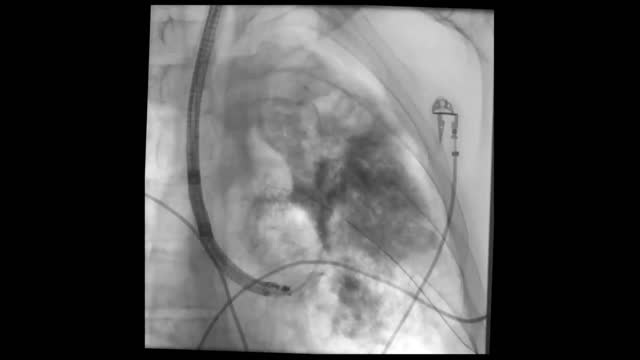

We report the case of a 55-year-old man, former smoker, diagnosed with very severe COPD and lung adenocarcinoma (cT1aN0M0) in the left upper lobe (LUL). After evaluation by the chest tumor committee, lung radiofrequency ablation (Cool-tip® electrode) was recommended. This procedure caused a tension pneumothorax that required chest tube drainage, resulting in a persistent air leak. To locate the segment in which the bronchopleural fistula (BPF) originated and to visualize its trajectory, we performed selective bronchogram (SB) of the LUL under deep sedation with propofol, using radioscopy-guided instillation of 10ml Omnipaque® iodohexol with a Combicath radiopaque catheter, revealing BPF in the apical segmental bronchus of the LUL (video 1).